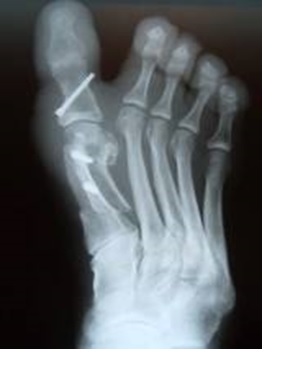

الطفلة نعيمة بكار البالغة من العمر عشر سنوات، والقاطنة بحي المنصور الذهبي بمدينة زاكورة، تعرضت لحادث دخول إبرة في رجلها، فقامت عائلتها بنقلها إلى مستشفى المدينة، فبدل أن يمدوا لهم يد العون قاموا بصد جميع الأبواب في وجههم. وأمرهم بنقلها إلى مدينة ورزازات، فقام أب الطلفة ع. بكار بنقل ابنته إلى مستشفى ورزازات ليتفاجأ برفض نزع الإبرة التي لا تزال بداخل رجلها إلى حد الآن، والغريب بأن المسؤولين في المستشفى يدعون بأنه لا يوجد عندهم المخدر (البنج) !!! ثم يتحايلون على أب الطفلة ويأمرونه بالعودة بها إلى مستشفى زاكورة من أجل التخدير ثم العودة بها مرة ثانية إلى مدينة ورزازات لنزع الإبرة من رجل الطفلة نعيمة !!!

ولهذا نناشد جميع المسؤولين للتدخل من أجل علاج الطفلة ونزع الإبرة من رجلها ونحن على أبواب الدخول المدرسي وعيد الأضحى.